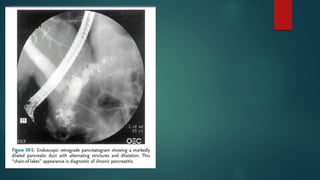

5. ERCP –

 Diagnostic as well as therapeutic

 Risk - 5%

 Diagnosis based on abnormalities in main pancreatic duct & side branches

 CHAIN OF LAKES Appearance

 Changes similar can also be seen with normal ageing

 Findings inchronic pancreatitis – Duct dilatation Duct obstruction Parenchymal heterogenity Irregular contour Calcification 4. MRI –  Duct Visualisation improved by secertin administration 5. ERCP –  Diagnostic as well as therapeutic  Risk - 5%  Diagnosis based on abnormalities in main pancreatic duct & side branches

 CHAIN OFLAKES Appearance  Changes similar can also be seen with normal ageing  CAMBRIDGE GRADING OF CHRONIC PANCREATITIS ON ERCP GRADE MAIN PANCREATIC DUCT SIDE BRANCHES NORMAL Normal Normal EQUIVOCAL Normal <3 Abnormal MILD Normal >/= 3 Abnormal MODERATE Abnormal “ SEVERE Abnormal with Large cavity >10mm) Obstruction Filling defects Severe dilatation / irregularity “